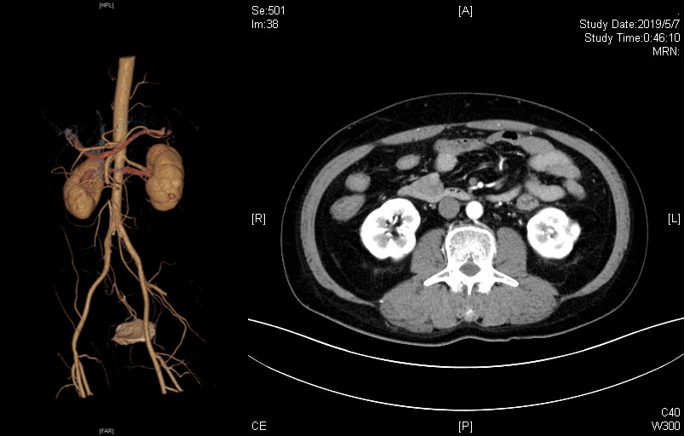

病例1:单纯腔内治疗

患者女性,72 岁,因 "腹痛 5 小时" 入院,既往房颤病史,未规律抗凝。腹腔镜探查未见肠道坏死,遂行腔内治疗,术后恢复良好,未发生肠切除及相关并发症。

图:术前检查